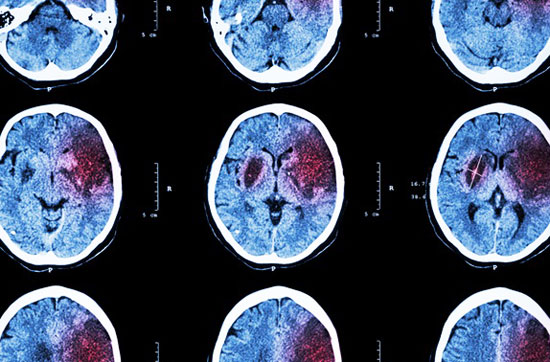

Dar dr. Hamer a dus cercetările sale cu un pas mai departe. Urmărind ipoteza că toate evenimentele din organism sunt controlate de creier, a analizat tomografiile pacienţilor săi şi le-a comparat cu istoricul lor medical. Dr. Hamer a descoperit că orice boală, nu numai cancerul, este controlată de o zonă din creier ce îi corespunde în mod specific şi este legată, în mod particular, de un eveniment traumatizant perfect identificabil. Mai exact, pe tomografiile realizate a sesizat apariţia unor aspecte anormale, sub forma unor cercuri concentrice în diferite zone ale creierului. Mai interesant era că oamenii cu acelaşi tip de cancer, aveau pe tomografii elemente anormale mai intense exact în aceleaşi zone ale creierului. Cu alte cuvinte, fiecare tip de cancer (organ) avea o zonă de corespondenţă în creier, care nu mai funcționa corect.

Analizând mii de tomografii (CT) în corelaţie cu istoricul pacientului, dr. Hamer a descoperit că, atunci când are loc DHS, şocul impactează o zonă specifică, predeterminată din creier, cauzând o anormalitate care este vizibilă pe tomografie, sub forma unui set clar de inele concentrice (în 1989, Siemens, producătorul german de aparate tomografice, a confirmat că aceste inele nu provin de la o proastă funcţionare a aparaturii). Astfel că dr. Hamer a ajuns să îşi dea seama ce organ/organe erau afectate la un pacient şi în ce mod, doar citind o tomografie a creierului.